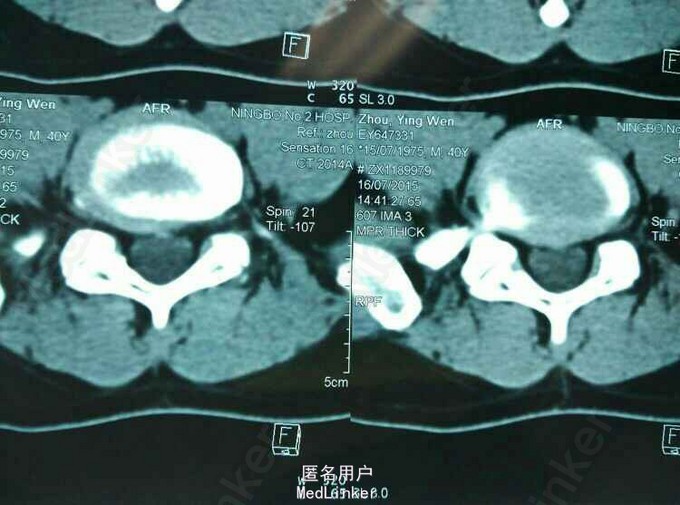

MRI及CT:L5S1 椎间盘脱出,向上游离。

诊断:L5S1椎间盘脱出(向上高度游离) 治疗:后路经椎板间入路椎间孔镜下髓核摘除,射频消融。